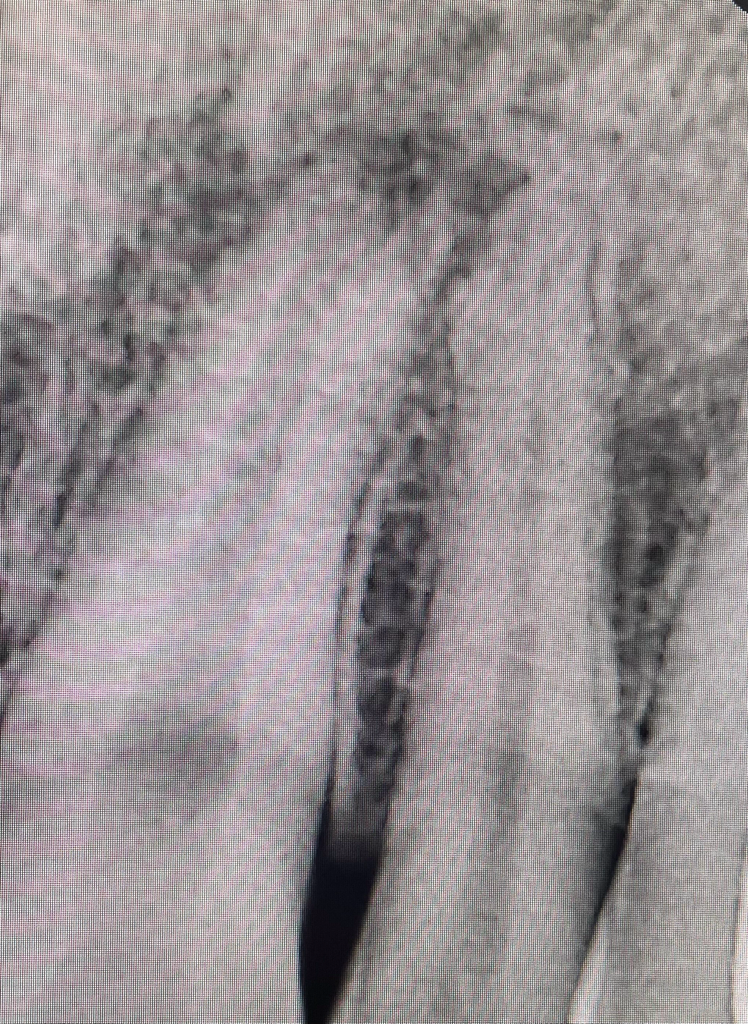

사진은 한달 전에 찍은 엑스레이 사진입니다

치근단의 옆에 있는 치아의 뿌리쪽은 현재 사진상으로는 이상이 없어보입니다.

옆에 치아 쪽으로 염증이 붙어 있는 것은 맞으나 지금으로서는 치료 이후에 옆에 치아도 치료를 해야할지, 정상적으로 회복될지는 상당히 애매한 위치라고 보여집니다. 너무 불안하시다면 대학병원이 아닌 일반 치과에서도 충분히 치료를 할 수 있으므로 방문해보는 것도 한 방법입니다.